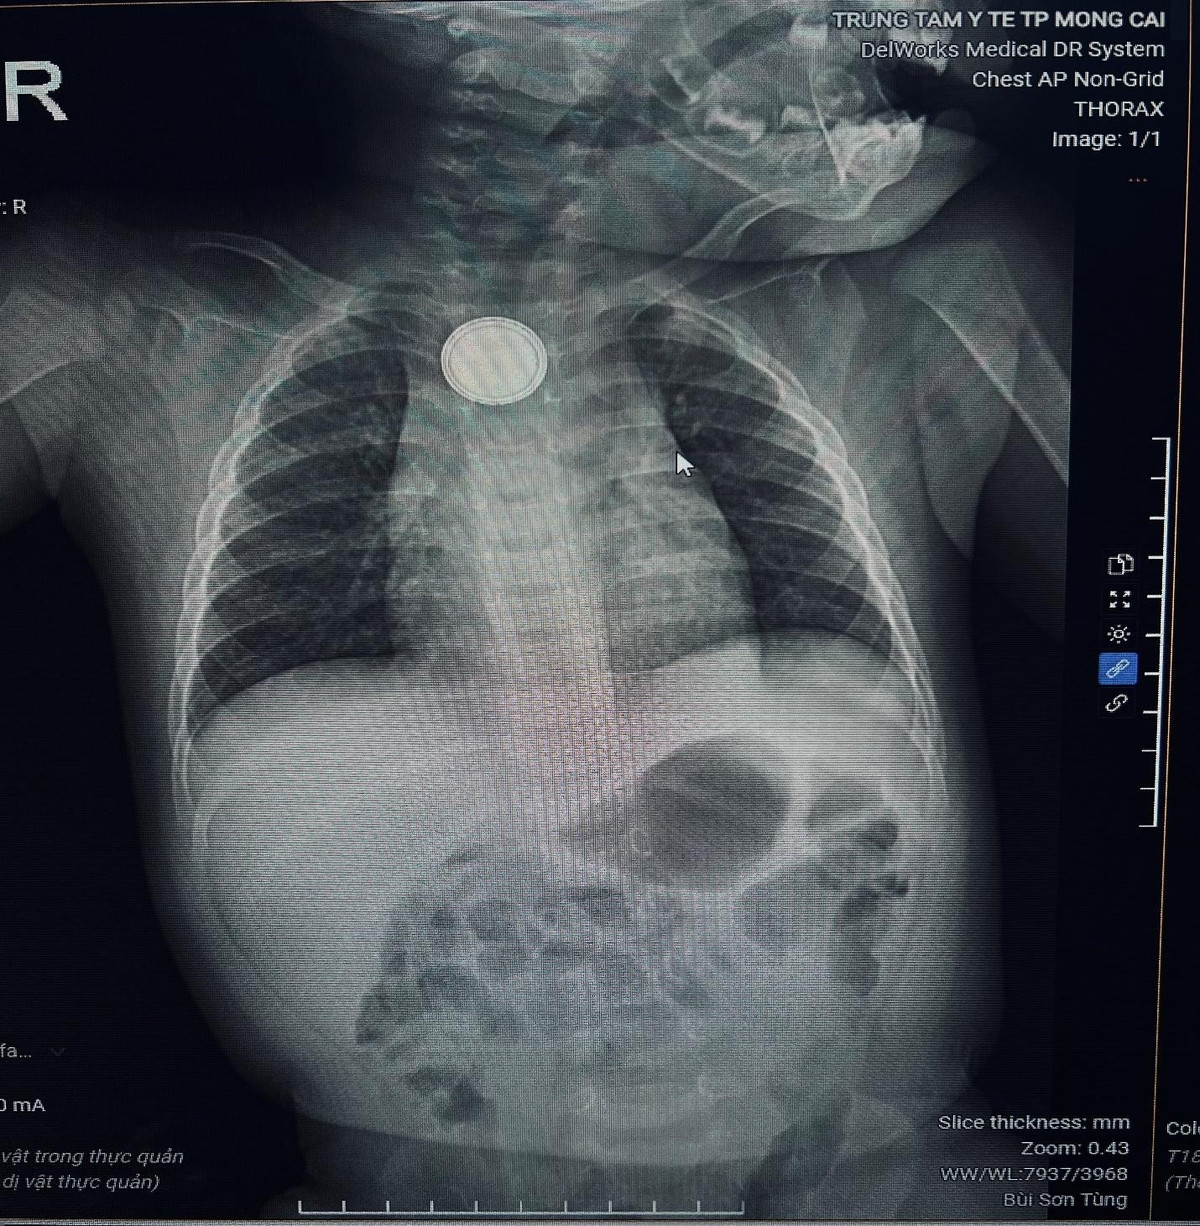

Trung tâm Y tế Móng Cái (Quảng Ninh) vừa tiếp nhận cấp cứu bệnh nhi B.M.K. (11 tháng tuổi) nhập viện trong tình trạng nôn nhiều, quấy khóc dữ dội. Qua thăm khám và chụp X-quang, các bác sĩ phát hiện dị vật kim loại hình tròn mắc kẹt tại thực quản.

Hình ảnh chụp Xquang phát hiện dị vật thực quản/ Ảnh Trung tâm Y tế Móng Cái